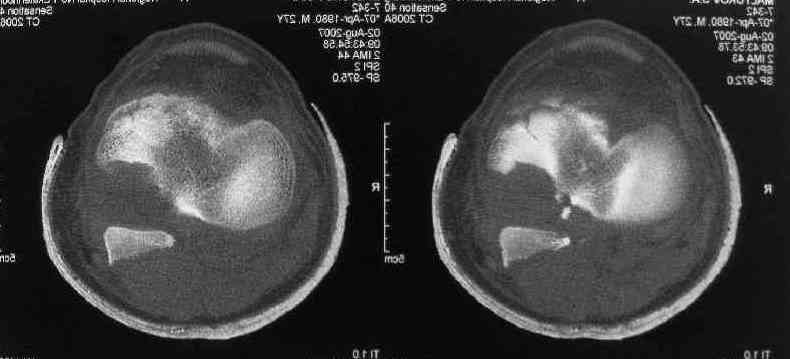

I thank for attaching the CT scan. it makes all the details very clear.

the approach should be standard posterior one (same that we use to fix the avulsed PCL).

the fragment is rotated and hence may require some manipulation, especially in flexion of the knee joint.

fixation may be with cancellous screw and washer.

Для определения доступа сагитальные срезы менее информативны, необходимо иметь корональные срезы.

Корональные срезы дают информацию об апексе перелома, и также информацию о вовлечения суставной поверхности, что является немаловажным для прогноза.

Операция из разряда травматологической "экзотики" прошла успешно. Доступ понравился:анатомичный, хорошая визуализация, удобно работать и оператору и ассистентам. Наложили пневможгут, но воспользовались им только на этапе ревизии сустава. Фрагмент развернулся на 90 град. на 2-ух "жгутах": медиально - сухожилие m.semitendinosus, латерально - задняя крестообразная связка. Мобилизовали,развернули и уложили на место без особого труда. Фиксировали отмоделированной 1/3-трубчатой пластиной. Мениск оказался неповрежден. Сустав стабилен. Обошлись без

иммобилизации, планируем начать ранние движения. Остальное на фото, дополнительно приложены корональные срезы КТ.